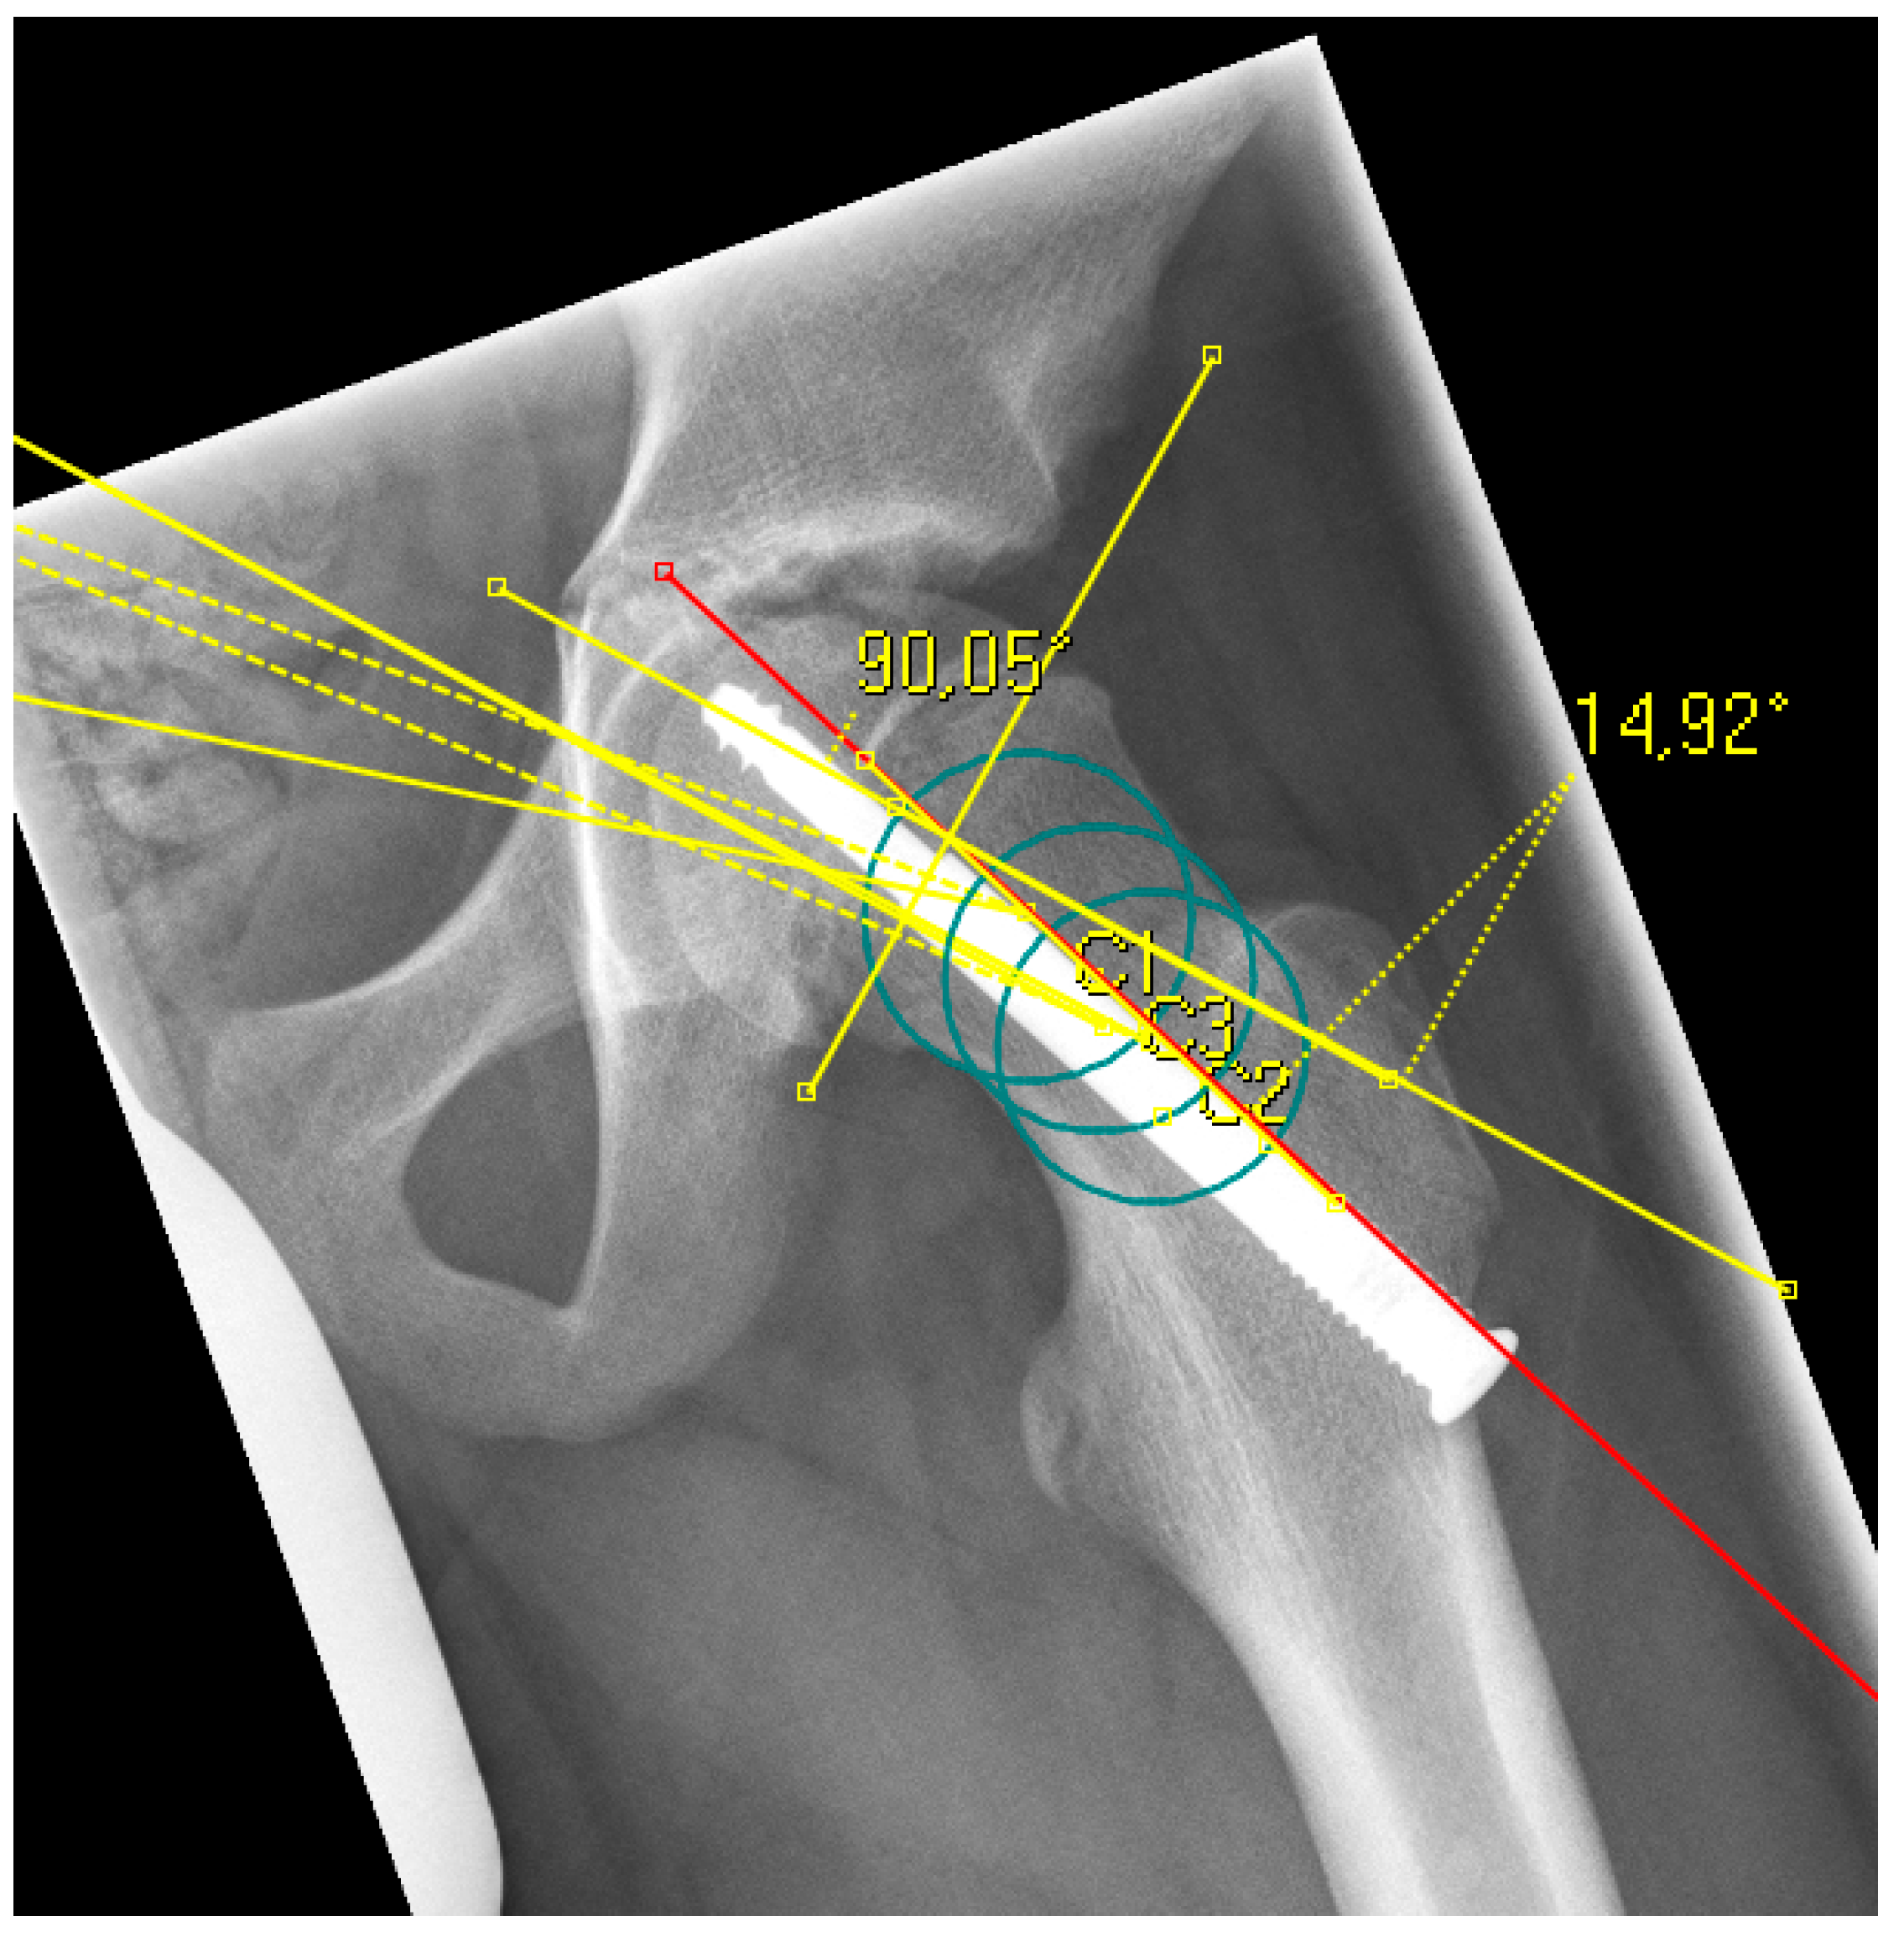

The radiological analysis directly after surgical fixation included the lateral center edge angle according to the sourcil method (LCEA) [22] and the acetabular angle (inclination) to evaluate the femoral coverage [23], especially regarding the presence of a hip dysplasia or coxa profunda, as well as the absolute slip angle according to Southwick [24,25]. The grading of the Southwick angle values is typically: mild (<30°), moderate (30–50°) and severe (>50°). Because the alpha angle is referenced to the femoral neck axis, this reference was the same for the posterior epiphyseal tilt to predict a FAI type cam over the time [26]. In contrast to the Southwick angle, which is determined as an angle between the slipped capital epiphysis and the femoral shaft axis, the posterior epiphyseal tilt was referenced also to the femoral neck axis like the alpha angle [27]. In addition, parameters for dysplasia resp. retroversion were evaluated, including the crossover sign (the anterior and posterior acetabular rims crossing on the pelvic a.p.) and the prominence of the ischial spine (PRISS; the ischial spine is projected in the lesser pelvic on the pelvic a.p.) [28]. In presence of a crossover sign and a positive PRISS a retroversion was assumed, whereas a dysplasia was defined with a LCEA <20 and an inclination >10°. All the described values were assessed again at the last time of the radiological follow-up, additionally the alpha angle [13]. In presence of a SCFE, the center of the femoral head is not always aligned to the axis of the femoral neck for measurement of the alpha angle and the posterior epiphyseal tilt. To avoid inaccuracy, the anatomical method according to Bouma et al. was used [29]. For this, the femoral neck axis was defined with three circles along the femoral neck, whichever fitted the bony neck best (Figure 1 and Figure 2).

Figure 2. Example of a radiograph with the measurement of the epiphyseal tilt based on the anatomical femoral neck axis (red line), which was determined with three circles (green) according to Bouma [29].